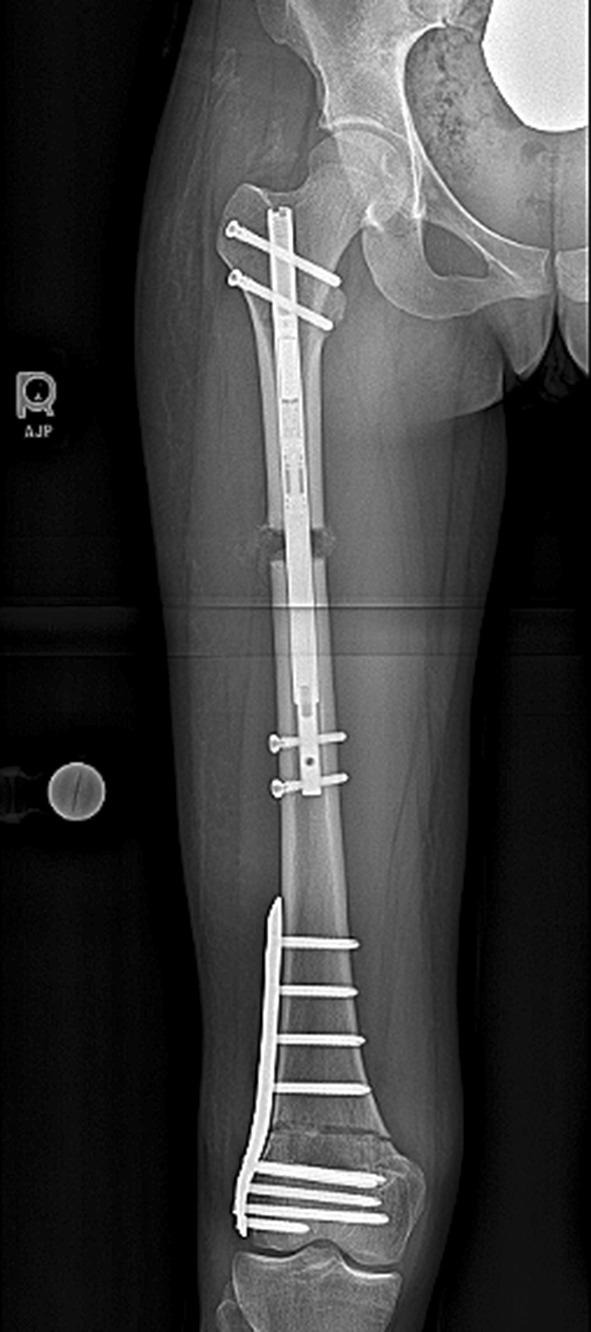

Salter Harris fractures of the distal femur can lead to growth disturbance with resulting leg length inequality and knee deformity. We have looked at a case series (3) of patients who presented with a distal femur flexion malunion and shortening treated with a distal femoral osteotomy and plating and a proximal femoral osteotomy with a magnetic internal lengthening nail. Does a two-level osteotomy and internal fixation approach provide a reliable result both radiographically and functionally? The average knee extension loss was 12°, LLD 47 mm, PDFA 65°, MAD 2 mm. The patients were treated with an acute, posterior, opening wedge osteotomy of the distal femur stabilized with a lateral plate and screws and grafted with cancellous chips and putty. A second osteotomy was made proximally in the femur percutaneously, and the internal lengthening nail was inserted. Lengthening was done at approximately 1 mm/day. The average extension gain was 12°; amount of lengthening at the proximal site was 40 mm, LLD was 3 mm. The average PDFA was 81°, and MAD 3 mm. There were no complications. Functional results were excellent. Bone healing index was 24 days/cm. The average distance from the distal osteotomy to the joint line was 57 mm. The technique of two-level femur osteotomy stabilized with a plate and lengthening nail yielded excellent results with acceptable correction of deformity, full knee extension, and improved function. There were no complications including implant failure, infection, need for blood transfusion, knee stiffness, nonunion, compartment syndrome, or malunion.

摘要